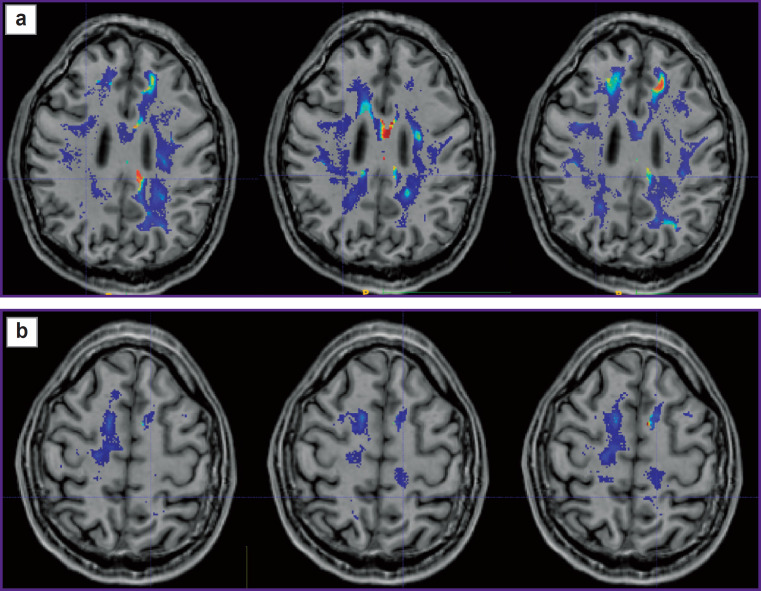

Results: During the investigation, we have developed an algorithm of DKI analysis and plotting the profile of tissue parameters in the direction from the tumor towards the unaffected white matter according to the data of standard MRI. Changes of the DKI indicators along the trajectories built using the proposed algorithm in the perifocal zone of glioblastoma and metastasis have been compared in this work. We obtained not only changes in the parameters (gradients in trajectory plots) but also a visual reflection (on color maps) of a known pathomorphology of the process - no significant gradients of DKI parameters were detected in the perifocal metastasis edema, since there was a pure vasogenic edema and no infiltrative component. In glioblastoma, gradients of DKI parameters were found not only in the zone of perifocal edema but beyond the zone of MR signal as well, which is believed to reflect diffusion disorders along the white matter fibers and different degrees of brain tissue infiltration by glioblastoma cells.

Conclusion: The developed algorithm of DKI analysis in brain tumors makes it possible to determine the degree of changes in the tissue microstructure in the perifocal zone of brain glioblastoma relative to the metastasis. The study aimed at obtaining individual maps of tumor invasion, which will be applied in planning neurosurgical and radiation treatment and for predicting directions of further growth of malignant gliomas.